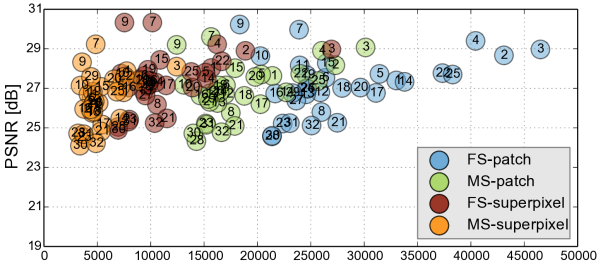

Reconstruction of Adult Brain MRI: Experiments on adult brain MR data using the Brainweb database [34] included introducing synthetic non-rigid motion artifacts as described in Sec. IV. Example slices of standard planes of original and corrupted data are depicted in Fig. 9. Comparative experimental results of SVR and PVR reconstruction methods are shown in Fig. 10 for PSNR, SSIM and CC. For all metrics, PVR shows an improved performance over SVR, particularly in presence of deformations with higher skewing angles. Further, we observe that superpixel-based PVR achieves similar performance as PVR using arbitrary square patches, while requiring a lower amount of input patches.

Comparative experiments of PVR variants were carried out on 32 fetal MR scans at gestational ages of approximately 20 weeks, presenting with challenging image corruption. Tab. I (a) & (b) show numerical results of evaluating individual stacks before reconstruction (baseline), and the final reconstructed image using square patches, superpixels and multi-scale variants of PVR. Statistical testing between baseline and PVR variants was carried out using paired T-Tests and differences between using fixed or multi-scale and using square patches or superpixels were assessed via Two-factor ANOVA with repeated measures. In Tab. I (a) & (b) the names of PVR variants are marked in bold if statistically significant differences have been found during analysis, i.e., FS and MS and/or Square Patches and Superpixel pairs are bold if the results between them differ significantly.

The evaluation of the reconstruction quality of a whole 3D image into a single-valued metric may not properly reflect the performance differences, as it is based on averaging values of all the pixels of all the input stacks. Furthermore, Tab. I indicates significant differences between variants of PVR but these differences have only minimal qualitative effect on reconstruction accuracy. Therefore, Fig. 12 evaluates the reconstruction quality of PVR additionally using dissimilarity heat maps based on the measured DSSIM (see Sec. IV-A). This approach allows further qualitative evaluation and allows for uncertainty visualization of PVR reconstructions.

Performance Analysis: We further evaluate the computational performance of each PVR variant. Measuring the overall runtime is not meaningful because this would be highly machine specific and would include data transfer overhead and non optimized functions. The runtime varied between 2000–4000s on our testing machines, depending on the system configuration. Instead we are analyzing the computational overhead introduced by PVR compared to SVR. The overhead can be measured by counting the number of processed patches and the number of additionally processed voxels. We compare these values to the achieved reconstruction quality in Fig. 13. Multi-scale superpixels show significantly better performance than other PVR variants and introduce the minimum necessary overhead while gaining the same image quality than more naïve PVR variants. Multi-scale superpixels are potentially five times faster than other variants.

PVR introduces a considerable computational overhead to the reconstruction stage of fetal MR image processing pipelines. We have evaluated the amount of necessary additional redundant information to give a general idea about the expected runtime of different PVR variants. Patches based on multi-scale superpixels are significantly more efficient than a naïve implementation of overlapping square patches, while maintaining a similar reconstruction accuracy. Quantitatively, square patches perform slightly better for the brain, which is most likely due to the rigid nature of the enclosing skull. Superpixel-based patches achieve better results for regions that are likely affected by non-rigid movements like the placenta and the whole uterus.